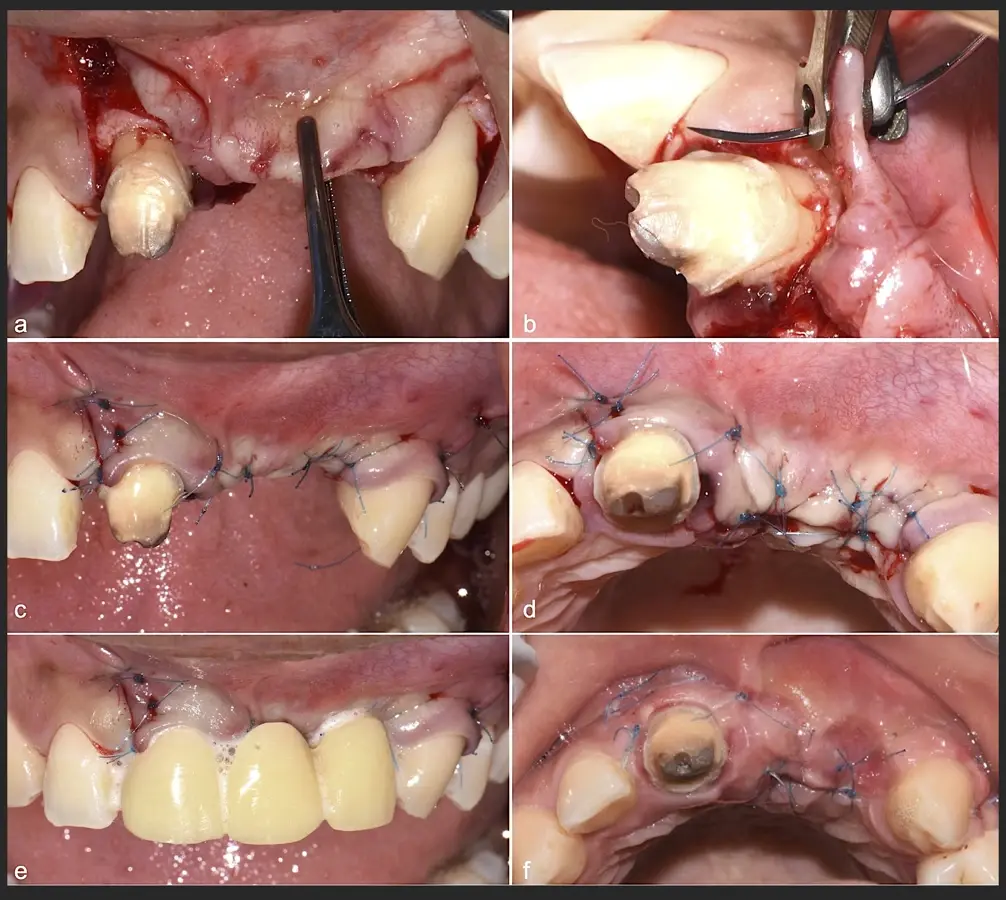

En las imágenes superiores se aprecia una reconstrucción de reborde con injertos en bloque previo a la planificación de implantes; en las imágenes inferiores, se observa la deficiencia vertical del reborde óseo y el tratamiento realizado con el piezoeléctrico.

Paciente de sexo femenino de 36 años de edad, llega a la consulta por presentar una restauración protésica inadecuada. En el examen clínico se observa una restauración protésica provisional acrílica sobre las piezas 1.1 y 2.2. Adicionalmente, se aprecia recesión gingival a nivel de la pieza 2.2 y deficiencia horizontal severa de reborde a nivel de la zona edéntula correspondiente a la pieza 2.1. En la evaluación tomográfica se observa ausencia total de tabla ósea vestibular en la pieza 2.2, y se corrobora el déficit en la zona edéntula de la pieza 2.1, para lo cual se indica una reconstrucción de estructuras óseas con hueso en bloque de origen bovino y posteriormente la colocación de implantes dentales.

Figura 45. Afrontamiento de colgajo y sutura (a - e). Control a los 7 días postquirúrgico (f).

El libro "Cirugía piezoeléctrica. Generalidades y aplicaciones clínicas" explica los fundamentos de esta tecnología y muestra su utilidad práctica en el consultorio mediante casos clínicos.